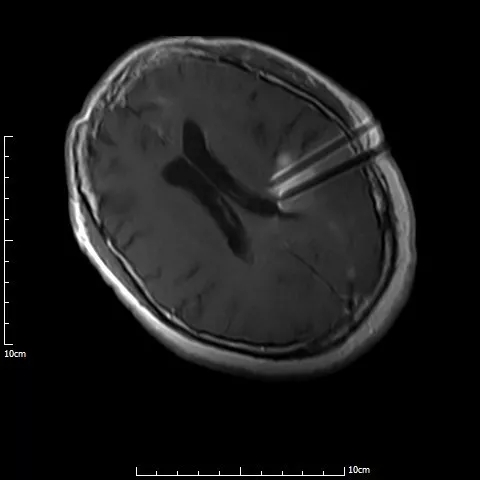

术中磁共振显示,4根穿刺针平行准确穿刺至病灶内

手术过程仅半小时,先对满女士进行局麻,然后在1.0T开放式介入磁共振监控及3D打印模板引导下,

李成利主任将4根磁共振兼容性穿刺针平行穿刺至肿瘤病变既定位置,根据近距离放疗计划植入I125放射性粒子,

该粒子通过持续释放低剂量γ射线对肿瘤细胞起到杀伤作用,而且对周边正常脑组织损伤较小。